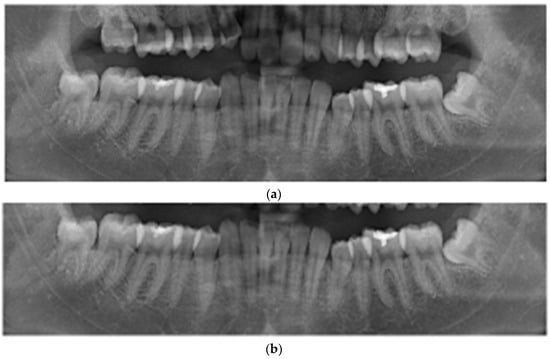

In the fields of medical imaging and oral surgical procedures, precise localization and identification of anatomical structures are of paramount importance. This is particularly evident when dealing with impacted teeth. Dentists must have a clear understanding of the patient’s oral condition before performing oral surgical procedures, especially for the precise positioning of the teeth and their proximity to the inferior alveolar nerve. Accurate positioning and identification not only contribute to surgical success but also reduce patient risk and discomfort. One such scenario involves impacted third molars, commonly known as wisdom teeth, which fail to erupt normally due to insufficient space in the jawbone [20]. The affected lower wisdom teeth may still be partially covered by soft tissue and unable to grow normally, as shown in Figure 1. The mandibular third molar may result in complications such as cysts and tumors [21], which can lead to nerve injuries, given the proximity of the lower third molars to the inferior alveolar nerve. Therefore, accurate knowledge of the location of the impacted tooth and its relative proximity to the inferior alveolar nerve (IAN) becomes critical during impacted tooth extraction surgery. In recent years, the development of computer vision and deep learning technologies has provided new avenues for addressing this challenge, including the application of techniques such as YOLO [22], Faster R-CNN [23], and image preprocessing algorithms. The integration of these techniques allows for accurate identification of the distance between the impacted tooth and the inferior alveolar nerve. It helps reduce potential nerve damage and improves the efficiency and safety of oral surgery.

Figure 1. DPR image in which the red circle encompasses the impacted tooth and the inferior alveolar nerve.